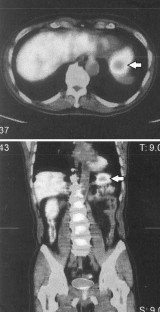

Fig. 1